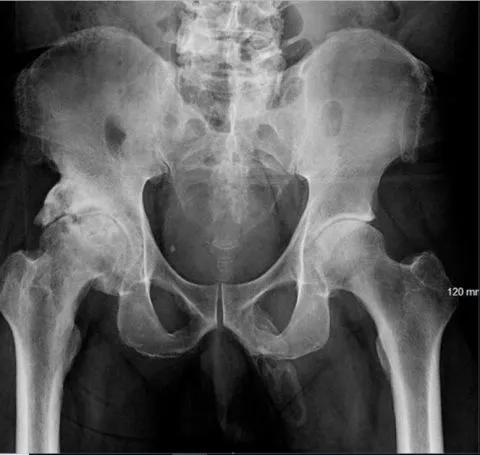

5.“陰莖骨化”

有時,身體會在不該長出的地方長出骨頭。對於一名 63 歲的男性來說,這發生在陰莖上。

根據發表在《泌尿外科病例報告》雜誌 9 月刊上的一份病例報告,該男子在跌倒後接受了骨盆 X 光檢查,醫生髮現他的整個陰莖軸都有“骨化” 。換句話說,他的陰莖正在變成骨頭。

該男子被診斷為“陰莖骨化”。這種情況非常罕見,醫學文獻中報道的病例不到 40 例。當鈣鹽在軟組織中積聚,導致骨骼形成時,就會發生骨化。